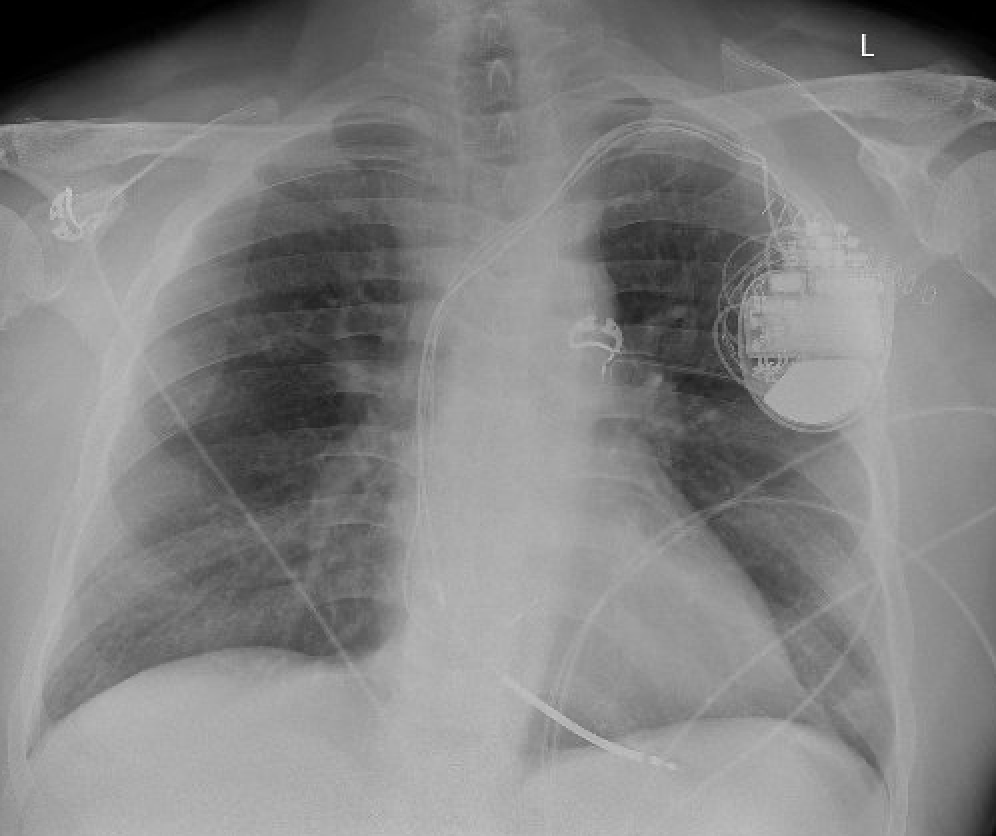

🚨 Case Spotlight: 70F with symptomatic bradycardia underwent dual-chamber pacemaker implant → chest pain + hypotension day 1 post-op 📸 Imaging: RV lead perforation + pericardial effusion 💬 Login & Join the discussion: LEADconnection.org #EPeeps #CIED #LeadManagement